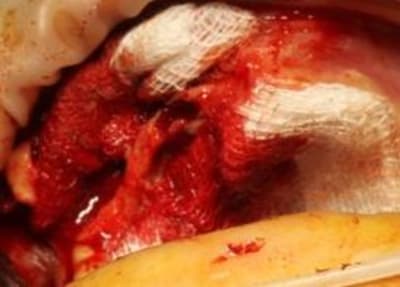

1 les séances d'ostéotension avait transformées le site, en quantité et qualité, j'aurais presque pu faire de l'expansion,mais les greffons étaient prêts, alors.

Comme prévu incision palatine à gauche , lambeau et après curetage de la zone 22, pose du greffon, ajustage parfait, vissage facile puisque les trous étaient faits (ainsi qu'une petite pièce de réparation pour la partie que j'avais abimé lors de la préparation

et du greffon)

et à droite, tunnelisation super simple.

merci Posit la reconstruction 3D était parfaitement fidèle et merci Raphaël Bardonnet (Biobank) le produit livré était parfait.

Seul Bémol, vidéo niet, le perchiste n'étant pas là nous avons loupé le vissage du premier greffon...et photos bof, D57 n'ayant pas pu se déplacer.

2, 3 photos quand même.

Bravo! succès à suivre... les photos de 2X2 imbibé de sang...moins spectaculaire...mais le but est atteint 2 blocs allogènes bien fixés en place avec incision minime...on voit quand même les points au niveau de l'ouverture pour la vis au niveau de la tunélisation c'est bien...Bravo maître... J'aimerais en savois plus sur le protocole des ostéotenseurs... Vous vous en servez en pré-op pour l'expansion?